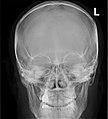

Paranasal Sinuses ant.jpg

Paranasal sinuses seen in a frontal view